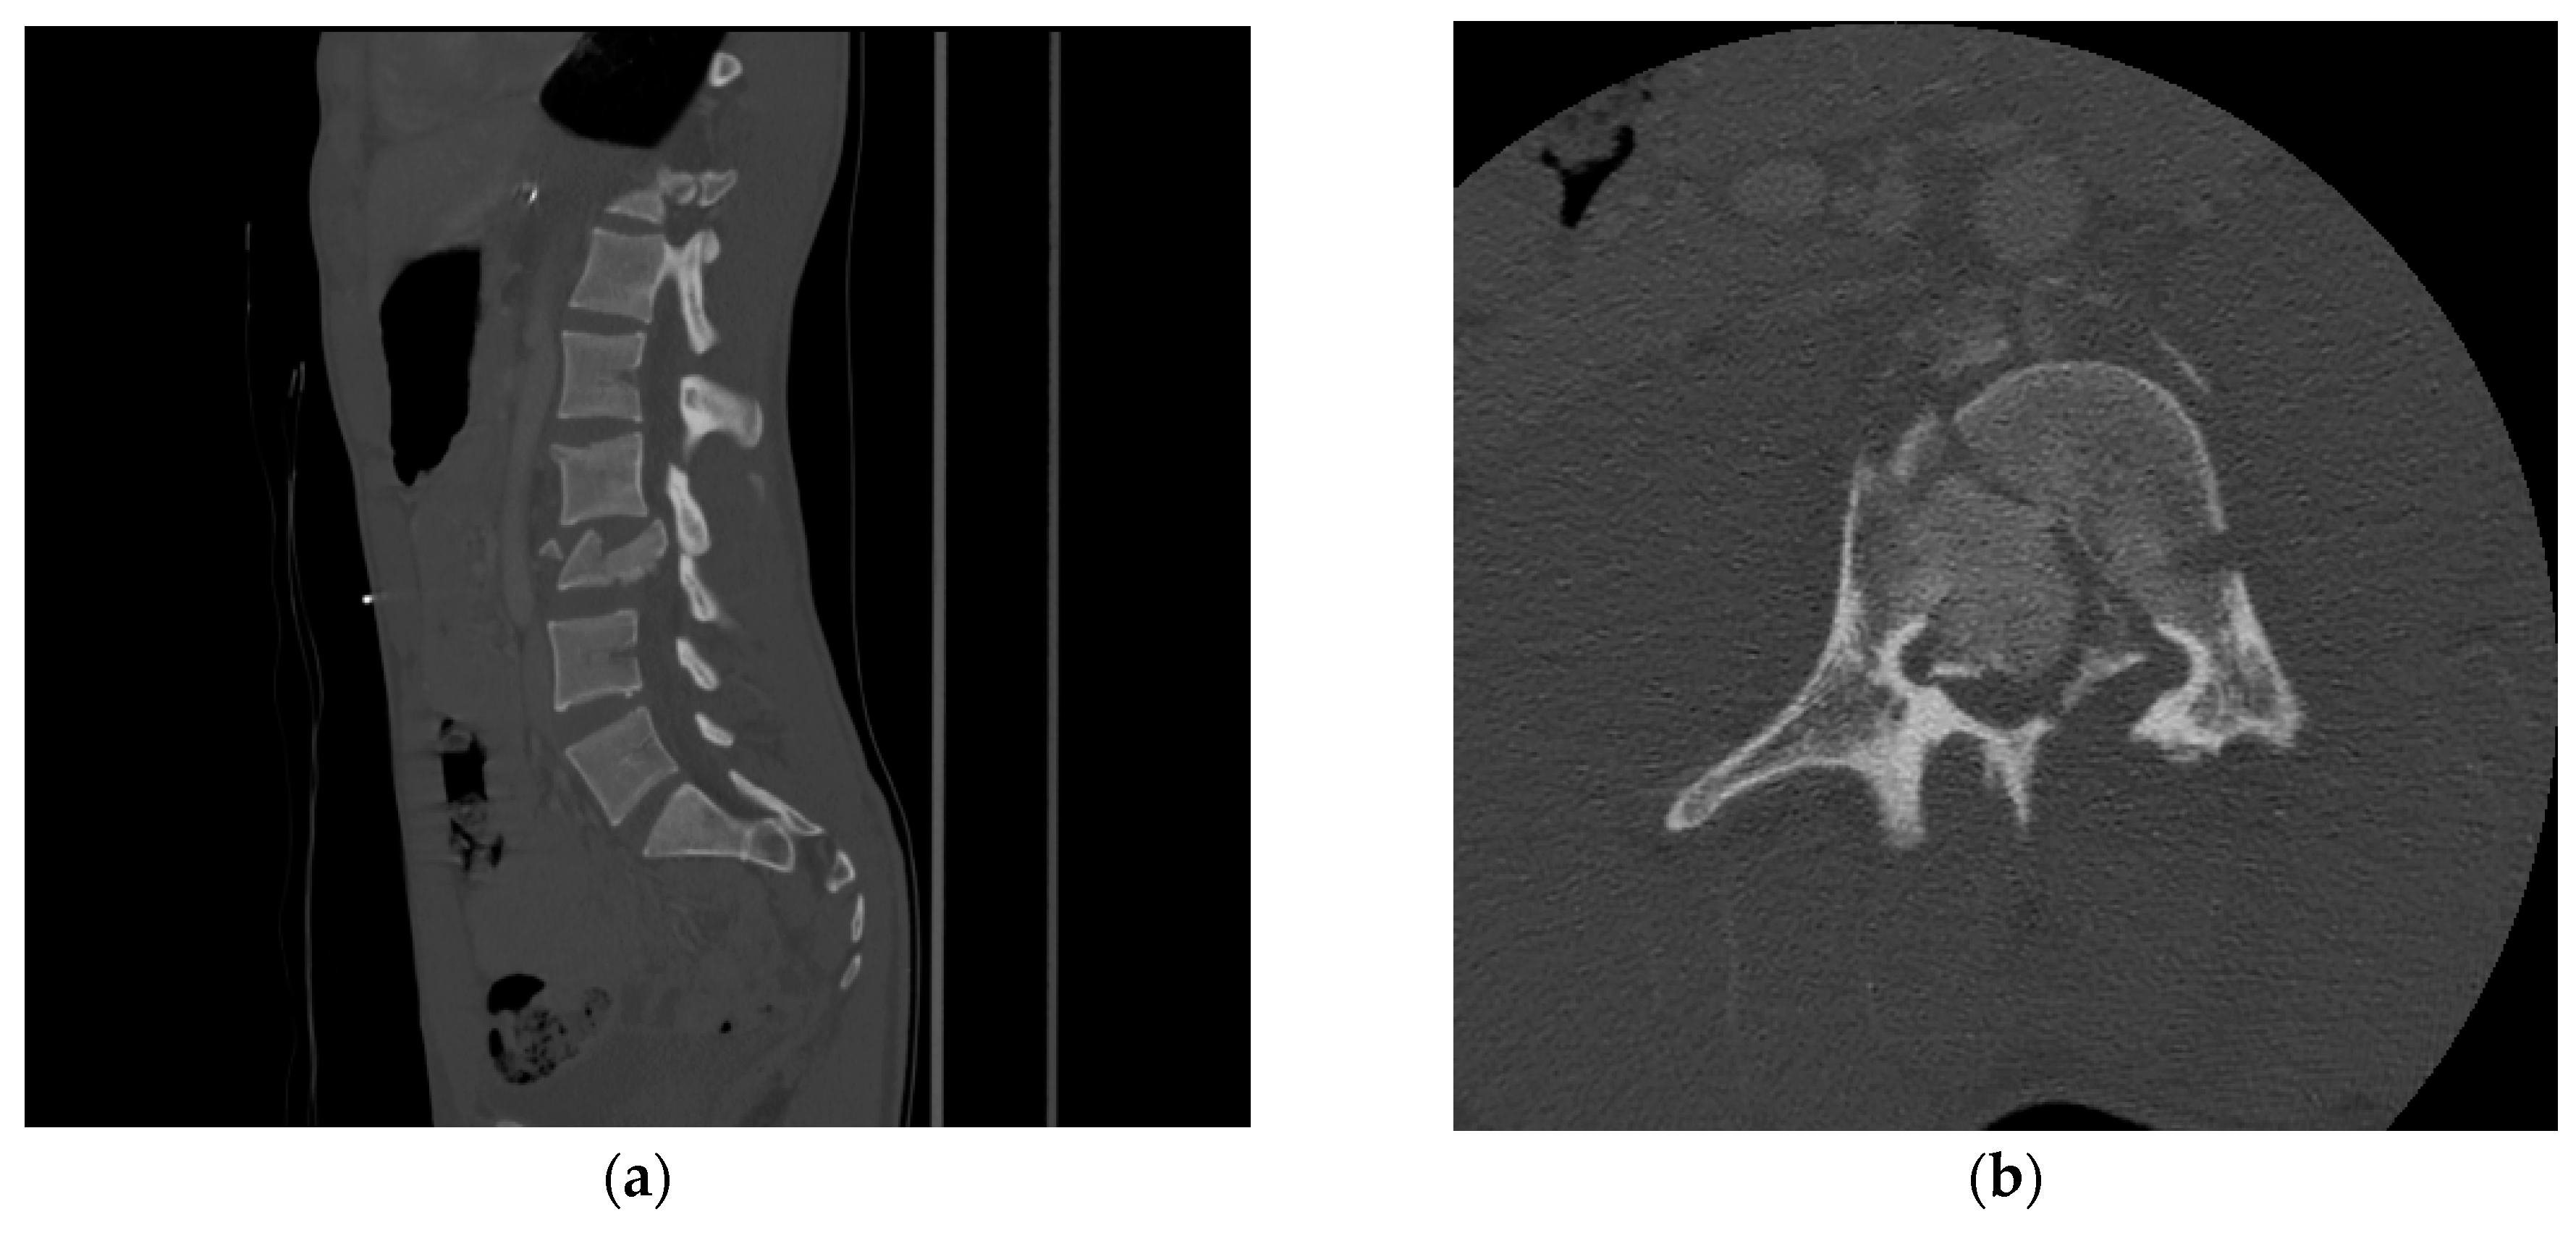

The American College of Radiology recommends CT as the initial imaging modality for the evaluation of spinal trauma in adults and children older than 14 years [6]. CT provides great detail regarding osseous anatomy and its associated pathology (Figure 1 and Figure 2) but can also reveal significant abnormalities such as traumatic disk herniations and epidural or subdural hematomas in the spinal canal.

Figure 1.

(a) Sagittal and (b) axial view of CT showing L3 burst fracture with significant retropulsion of the vertebral body into the spinal canal and loss of body heigh. There is involvement of the posterior elements.

Figure 2.

(a) Sagittal and (b) coronal view of CT showing type II dens fracture. “C1–C4” Designate each corresponding spinal level.